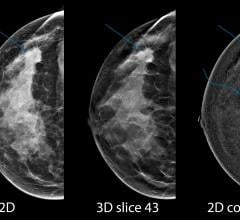

Professor Christiane Kuhl, M.D., director of radiology, University Hospital Aachen, Germany, explains how breast ...

Professor Christiane Kuhl, M.D., director of radiology, University Hospital Aachen, Germany, explains what it means to ...